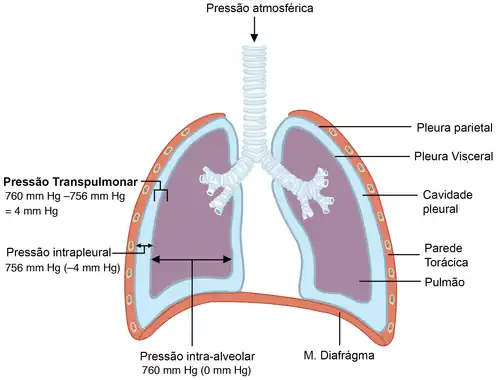

As pleuras parietal e visceral que revestem o pulmão formam um espaço virtual (não existente em condições fisiológicas) preenchido por lubrificante. Devido à força elástica de retração e à tensão superficial (forças do pulmão), a parade pleural em contato com o pulmão, pleura visceral, tende a se retraír. No entanto, a parede externa, parietal, mantém relação com a parede torácica e, assim, tende a ser abduzida (puxada para fora do centro do corpo). Assim, como cada parede tende a ser deslocada para sentidos diferentes, o volume intrapleural é maior e, portanto, a pressão intrapleural é naturalmente negativa. Esse fato terá consequências importantes para o estabelecimento da Pressão Transpulmonar ().

A diferença entre as pressões e determina a Pressão Transpulmonar (). Como normalmente a pressão intrapleural é negativa, em estado fisiológico, a Pressão Transpulmonar é positiva. Isso é determinante para que os alvéolos se mantenham abertos e não entrem em colapso. Em condições patológicas, como o pneumotórax, causado pela perfuração da pleura, a pressão intrapleural se equiliza com a pressão atmosférica e, assim, torna-se igual a 0. Nesse caso, torna-se negativa e os alvéolos sucumbam à pressão externa da pleura sobre o pulmão. [6][7]

- Na fase inicial da inspiração passiva, o músculo diafragma sofre contração, empurrando o conteúdo abdominal para baixo. Os intercostais externos se contraem, puxando a caixa torácica para cima. A ação destes dois músculos expande a caixa torácica;

- Expansão da caixa torácica causa aumento do volume intrapleural, cuja parede parietal é aderida à parede torácica. Consequentemente, a Pressão intrapleural se torna mais negativa;

- Diminuição da pressão Intrapleural leva ao aumento da Pressão Transpulmonar, leando à expansão de ;

- Expansão dos alvéolos ocasiona diminuição da ;

- (mais negativa que o meio externo) provoca inspiração de ar atmosférico para os alvéolos.